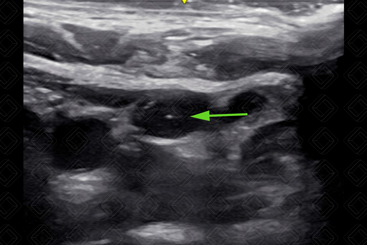

6. Avaliar compressibilidade do vaso (diferenciar artéria de veia) (Figura 3).

Texto alternativo para a imagem Figura 3. Veia jugular interna após compressão com transdutor (seta vermelha). Créditos: Dr. Igor Biscotto - Rio de Janeiro/RJ.